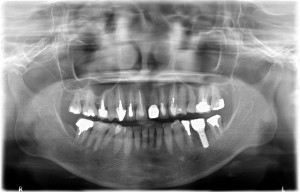

複数の歯に及び歯が失われているためCT画像上で診断と設計を行い、理想的な位置に歯を作ることができるように、サージカルガイドと言われるインプラント手術補助用マウスピースを用いてインプラント手術を行った。

術前レントゲン写真

-

術後レントゲン写真